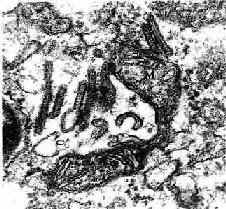

图10-6 郎格汉斯细胞电镜像 ×7800

↑球拍形Birbeck颗粒 M线粒体

(白求恩医科大学尹昕、朱秀雄教授供图)

2.郎格汉斯细胞 郎格汉斯细胞(Langerhans cell)由胚胎期的骨髓发生,以后迁移到皮肤内,分散在表皮的棘细胞之间。它们在身体各部位的数目不等,每平方毫米约为400~1000个。它们是多突起的细胞,在HE染色的切片上不易辨认。用三磷酸腺苷酶等特殊染色法可见细胞向周围伸出几个较粗的突起,这些突起又分出多个树枝状的细突起。穿插在棘细胞之间(图10-5)。电镜下可见细胞具有以下的特点:①胞核呈弯曲形或分叶形;②胞质密度低,无角蛋白丝和桥粒;③胞质内有特殊形状的伯贝克颗粒(Birbeck granule),有膜包裹,呈盘状或偏囊形,长15~30nm ,宽4nm,一端或两端常有泡,颗粒的切面为杆状或球拍形,内有纵向的致密线(图10-6,10-7),颗粒的意义尚不了解。这种细胞的性质与免疫系统的树突状细胞很相似,能识别、结合和处理侵入皮肤的抗原,并把抗原传送给T细胞,是皮肤免疫功能的重要细胞,在对抗侵入皮肤的病毒和监视表皮癌变细胞方面起重要作用,并在排斥移植的异体组织中起重要作用。